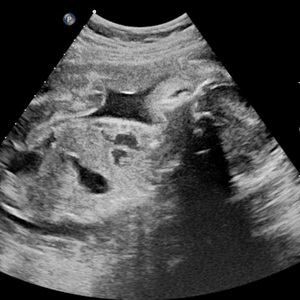

终于轮到我了。我绷紧神经,先到床头拿了一张纸放在床中央,坐上去准备脱右腿裤子时,突然发现自己穿了靴子,两只都脱,会耗时过长,大脑飞速转过医生等得不耐烦的样子,顿时慌乱了。“两只鞋子都要脱吗?”我问医生,问完我就后悔了。等待她的回答很漫长,长到我有足够时间把它们都脱下来。医生最终也没理我,撕开一个好像安全套似的袋子,取出套子,套在一根长长的检查器上,然后板着脸把它插进阴部。

我的心情非常复杂,不敢喊疼又有些恐惧。“多大了?”医生面无表情问我。“我吗?”我不清楚她问的是我,还是腹中的胎儿。

“几个月了?”她补充了一句。

“我不知道,医生没说,我自己查是5周。”

“还看不到。”她拔出检查器,打出检查单,“下一个。”

我的心凉了半截,慌乱穿好裤子,接过检查单,再次上楼进了医生办公室,里面已经有七八个人,我学着其他孕妇的样子,把B超单放在白口罩医生桌上,她扫了一眼,小声含糊说:“孕期太小了还看不到,下周再过来复查一次。”然后在打印机上又刷出了四五张单子,递给我:“验血,下周拿报告”。